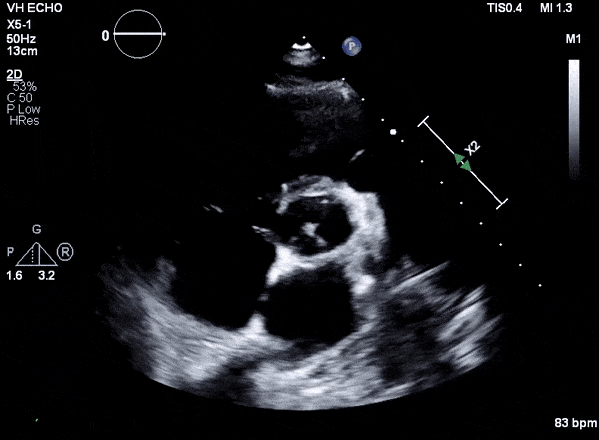

Case 2 (Pulmonic Valve IE)